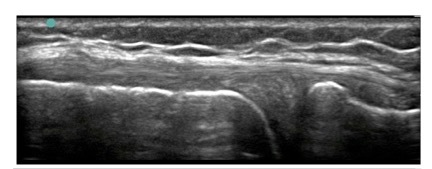

Knee Medial Collateral Ligament (MCL) Thickened Diffuse Inflammatory Tendinosis Image